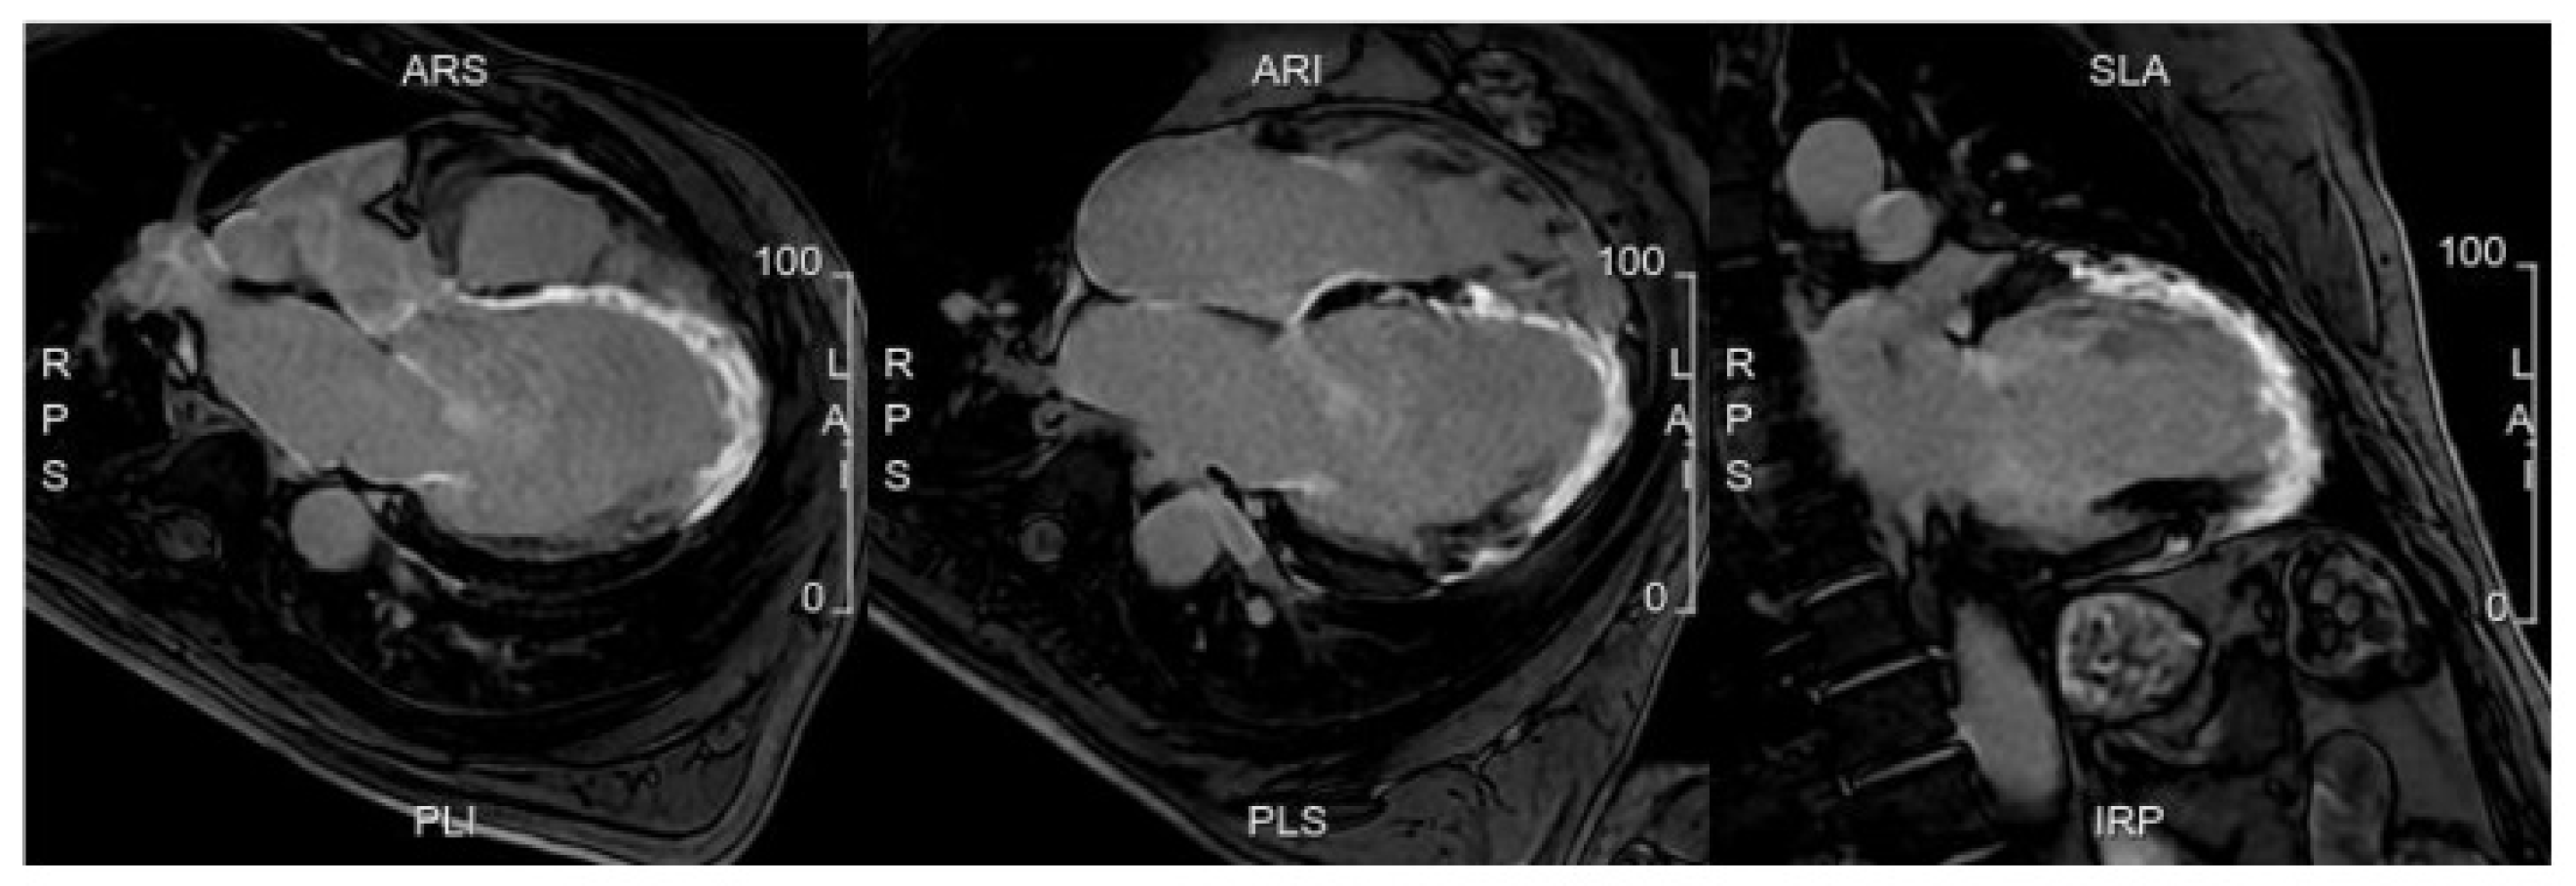

5.3. Advances in MRI for Risk Assessment